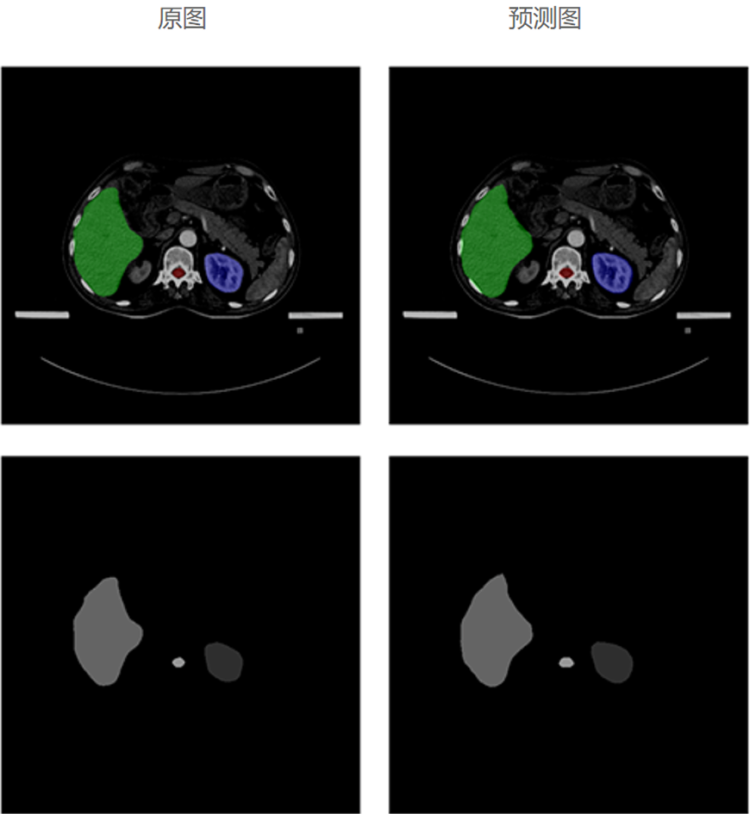

自动勾画效果

基于海量优选的专家勾画结构数据,利用深度学习人工智能技术,大力发展放疗智能勾画,自动勾画出精准且符合病人个性化特性的结果,帮助医生更加快速、准确地勾画肿瘤靶区和危及器官,从而推动放疗乃至肿瘤医疗的精准化、智能化发展,大大提高放疗勾画的工作效率。

模型经过对海量勾画结构数据的学习,以及改进优化,再进过大量样本数据训练及验证,自动勾画结果的平均准确度已达92%以上。